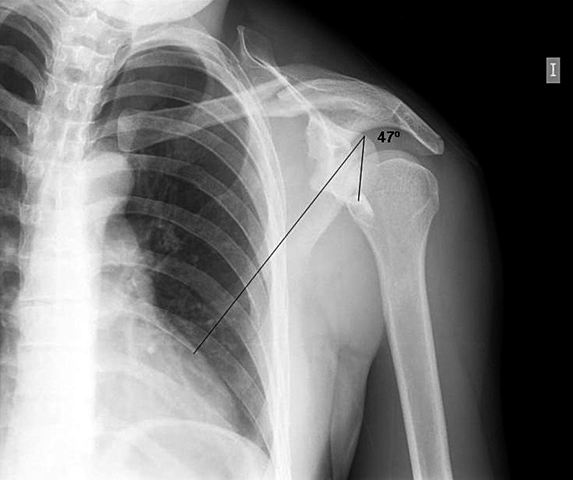

• Aplicación de la Radiología al Sistema Oseo

Aplicación de la Radiología al Sistema Oseo

Alban Köhler, uno de los grandes investigadores en este campo, publicó un libro titulado "Enciclopedia de los limites normales en las imagenes Röntgen". Pronto se dio cuenta de que, mediante

el uso de rayos X, era posible examinar problemas reumáticos

congénitos, además de afecciones metabólicas anormales y trastornos de osificación del esqueleto.